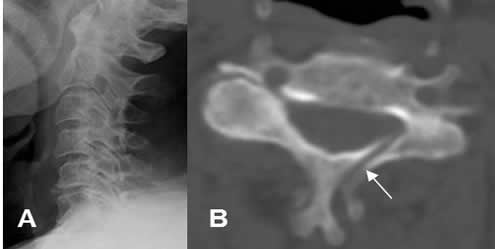

La tomografía axial computarizada (TAC) está indicada en el estudio de zonas anatómicas complejas, por la superposición de estructuras, como el hombro, el codo, la cadera, el tobillo, la columna y la cara. Esta modalidad permite detectar mas fracturas, la posición de los fragmentos, la presencia de cuerpos libres, el compromiso intra-articular y la valoración de la consolidación. En ocasiones son útiles las reconstrucciones sagitales y coronales, para una mejor caracterización. (1, 2, 3). (Fig 18 y 19).

Fig 18. Fractura no vista en Rx.

A: Rx lateral. Rectificación cervical, sin desalineación, ni fracturas. Calcificación en la parte anterior del disco C5-C6.

B: TAC axial. Fractura oblicua y no desplazada en la lámina izquierda de C5, no sospechada con la Rx.